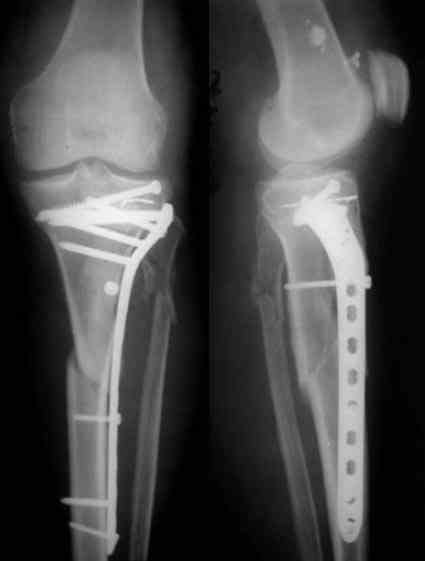

В заключение - клинический пример хирургического лечения похожего перелома из моего архива (1,2). После анатомичной репозиции суставной поверхности с введением стягивающего винта замещён дефект (3,4). Метадиафизарная часть перелома шинирована блокированной пластиной без обнажения отломков (5,6,7).